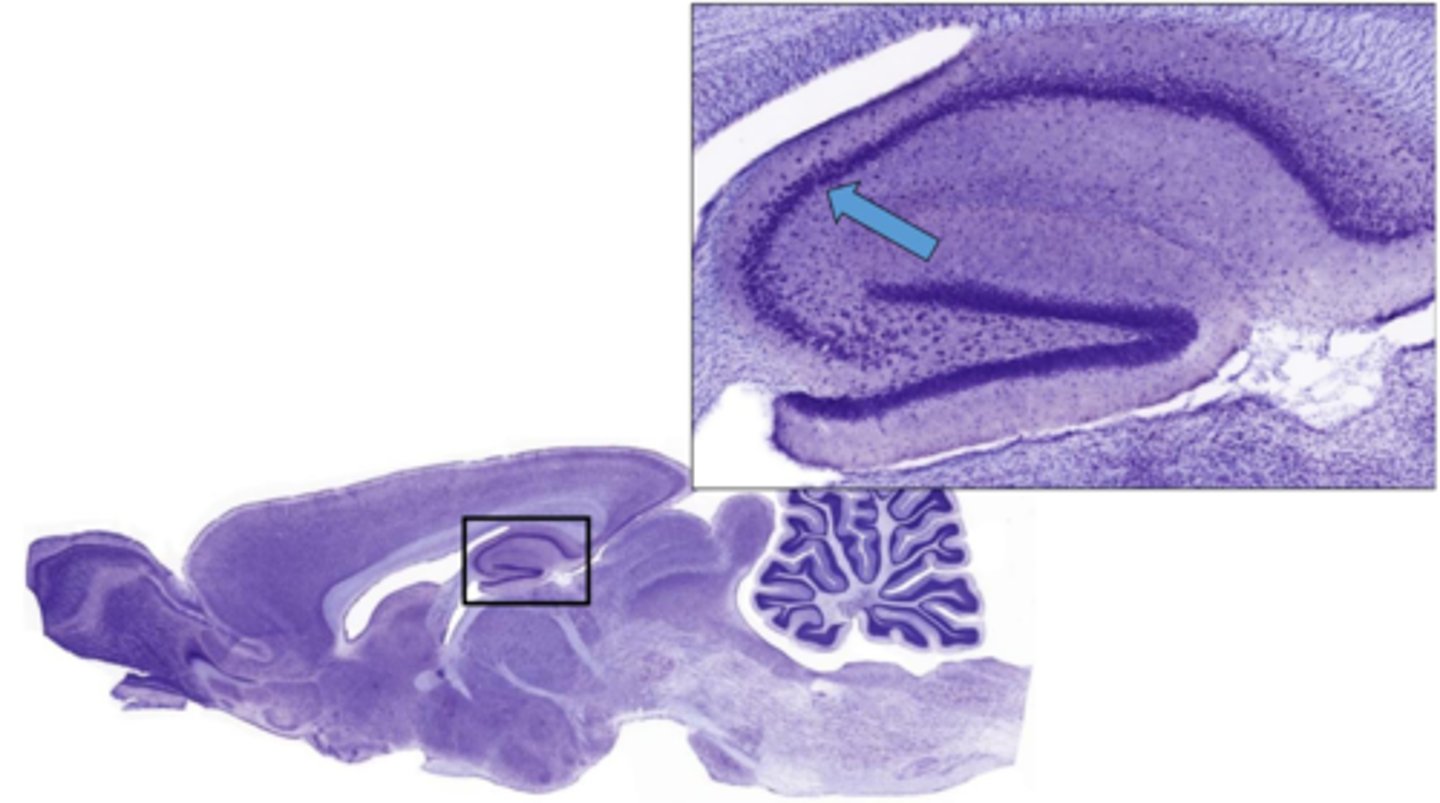

Identify the specific part of the brain

cerebrum

Identify the portion of the CNS

cerebellum

Identify the specific part of the brain in the inset

hippocampus

What part of the hippocampus is at 5 and 6

dentate gyrus